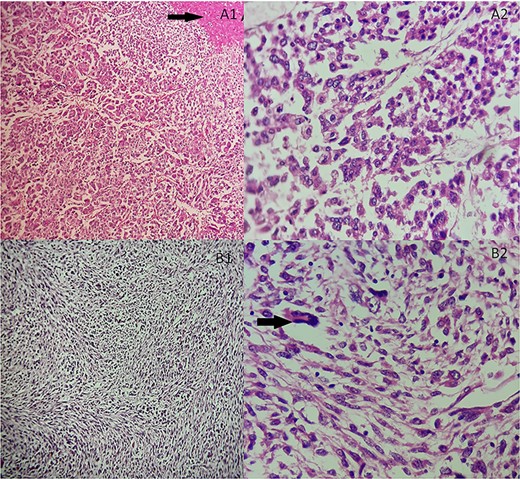

She underwent an adrenalectomy. On gross, the specimen weighed 660 g and measured 12 × 9 × 7 cm. It was well circumscribed, firm, beige-colored, with extensive hemorrhage and necrosis at sectioning; completely effacing the adrenal gland. Hematoxylin–eosin stained sections revealed diffuse sheets of epithelioid and pleomorphic/spindled cells. The epithelioid component consisted of sheets and nests of polygonal cells with clear and eosinophilic (40%) cytoplasm resembling adrenocortical cells with loss of lobulation (Fig. 2A). There was marked nuclear atypia (Nuclear grade III) with high mitotic activity (5/10 high-power fields [HPF]). The pleomorphic component (40% of tumor) consisted of fascicles of spindled and ovoid cells. Nuclei were highly pleomorphic with dense heterogenous chromatin (Fig. 2B). Some multinucleated neoplastic giant cells were identified. The mitotic count was higher (12 mitoses/10 HPF). The Weiss score was 6. On immunohistochemistry, epitheliod cells showed strong, diffuse positivity with Melan-A and synaptophysin. Spindled cells were focally strongly positive for synaptophysin, Melan-A and PS100 (Fig. 3). Immunostains for AE1/AE3, HMB-45, inhibin, desmin, vimentin, caldesmon and SMA were negative in both components. Unfortunately, genetic analysis was not performed, because it is not available in our institution. After a follow-up of 6 months, there was no evidence of local recurrence on CT.

(A) Adrenocortical sarcomatoid carcinoma histological features Carcinomatous component showing sheets and nests of epithelioid cells and necrosis (black arrow). (A1) Hematoxylin and eosin, ×100. (A2) Hematoxylin and eosin, ×400. (B) Adrenocortical sarcomatoid carcinoma histological features: sarcomatous component consisted of spindle-shaped and ovoid cells arranged in fascicular pattern. Associated to some multinucleated neoplastic giant cells (black arrow). (B1) Hematoxylin and eosin, ×200. (B2) Hematoxylin and eosin, ×400.